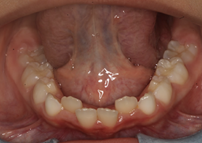

En el examen intraoral se observa mordida cruzada anterior. Las líneas medias dentales coinciden. Esto indica correcta alineación central. Tanto el arco superior como el inferior presentan forma en U, lo que sugiere un buen espacio para la dentición y una correcta disposición de los dientes en ambos arcos.

Figura 4. Mordida cruzada anterior Figura 5. Arco superior en forma de U

Figura 6. Arco interior en forma de U

La relación molar tanto del lado derecho como del izquierdo se clasifica como Clase I, indicando una correcta intercuspidación molar y oclusión funcional bilateral. Esto sugiere un buen equilibrio dentoalveolar y favorece la estabilidad oclusal general.

Figura 7. Relación molar derecha Figura 8. Relación molar izquierda